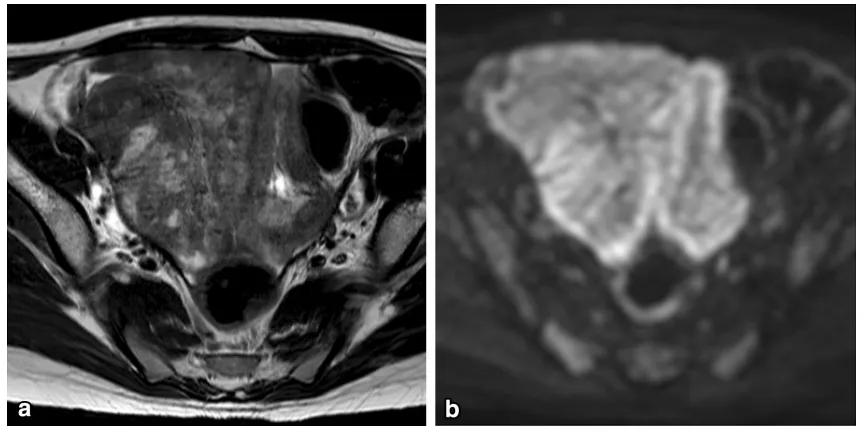

卵巢原发淋巴瘤罕见,常见组织学类型为弥漫大 B 细胞淋巴瘤及 Burkitt 淋巴瘤,后者常见于儿童及青少年。最常见的症状是腹部疼痛。原发继发影像表现一致,影像鉴别困难。常见表现为双侧卵巢实性肿物,T2WI 呈较信号均匀,内可见高信号分隔,增强扫描明显强化。肿物边缘多发线样排列的囊性结节,为「卵泡保留征」。

女,12 岁,卵巢 Burkitt 淋巴瘤。双侧卵巢肿物,T2WI 信号稍高(图 a),DWI 呈高信号(图 b),增强扫描明显强化(图 c),箭头显示肿物边缘多发囊性结节,为卵泡保留征。